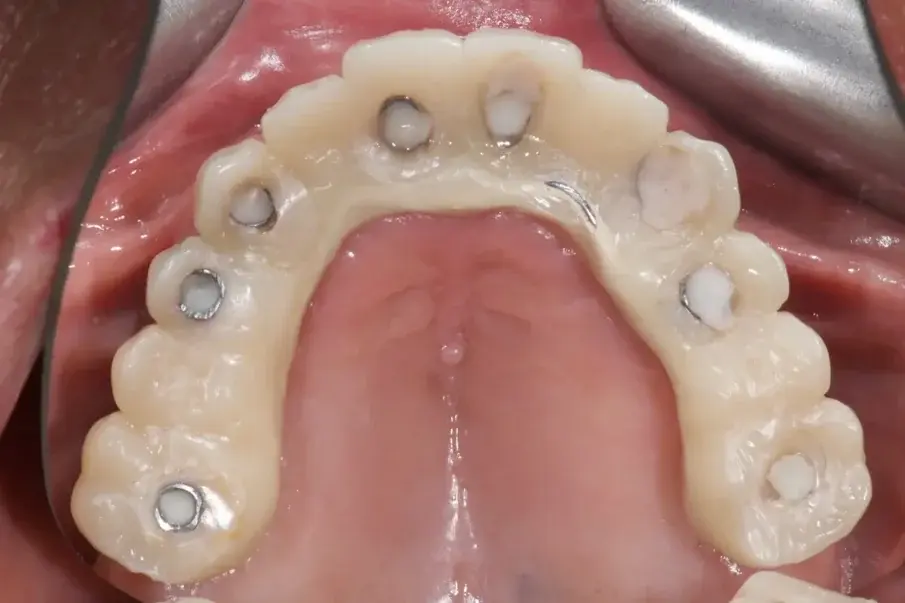

Фиг. 2: Начална ситуация, оклузален изглед.

85-годишен пациент с частично обеззъбяване беше насочен към нашата клиника за рехабилитация на цялата горночелюстна дъга. Пациентът беше в добро общо здравословно състояние, непушач. Основните му оплаквания включваха затруднения при дъвчене, болка в горната челюст и периодична халитоза. Клиничната и рентгенографската оценка разкриха фиксирана металокерамична протеза с къс обхват, задържана върху седем предни зъба на горната челюст. Протезата се беше отлепила и четири от опорните зъби бяха структурно увредени. Останалите три показваха различна степен на кариес и пародонтални проблеми. Беше поставена диагноза за компрометирано съзъбие.